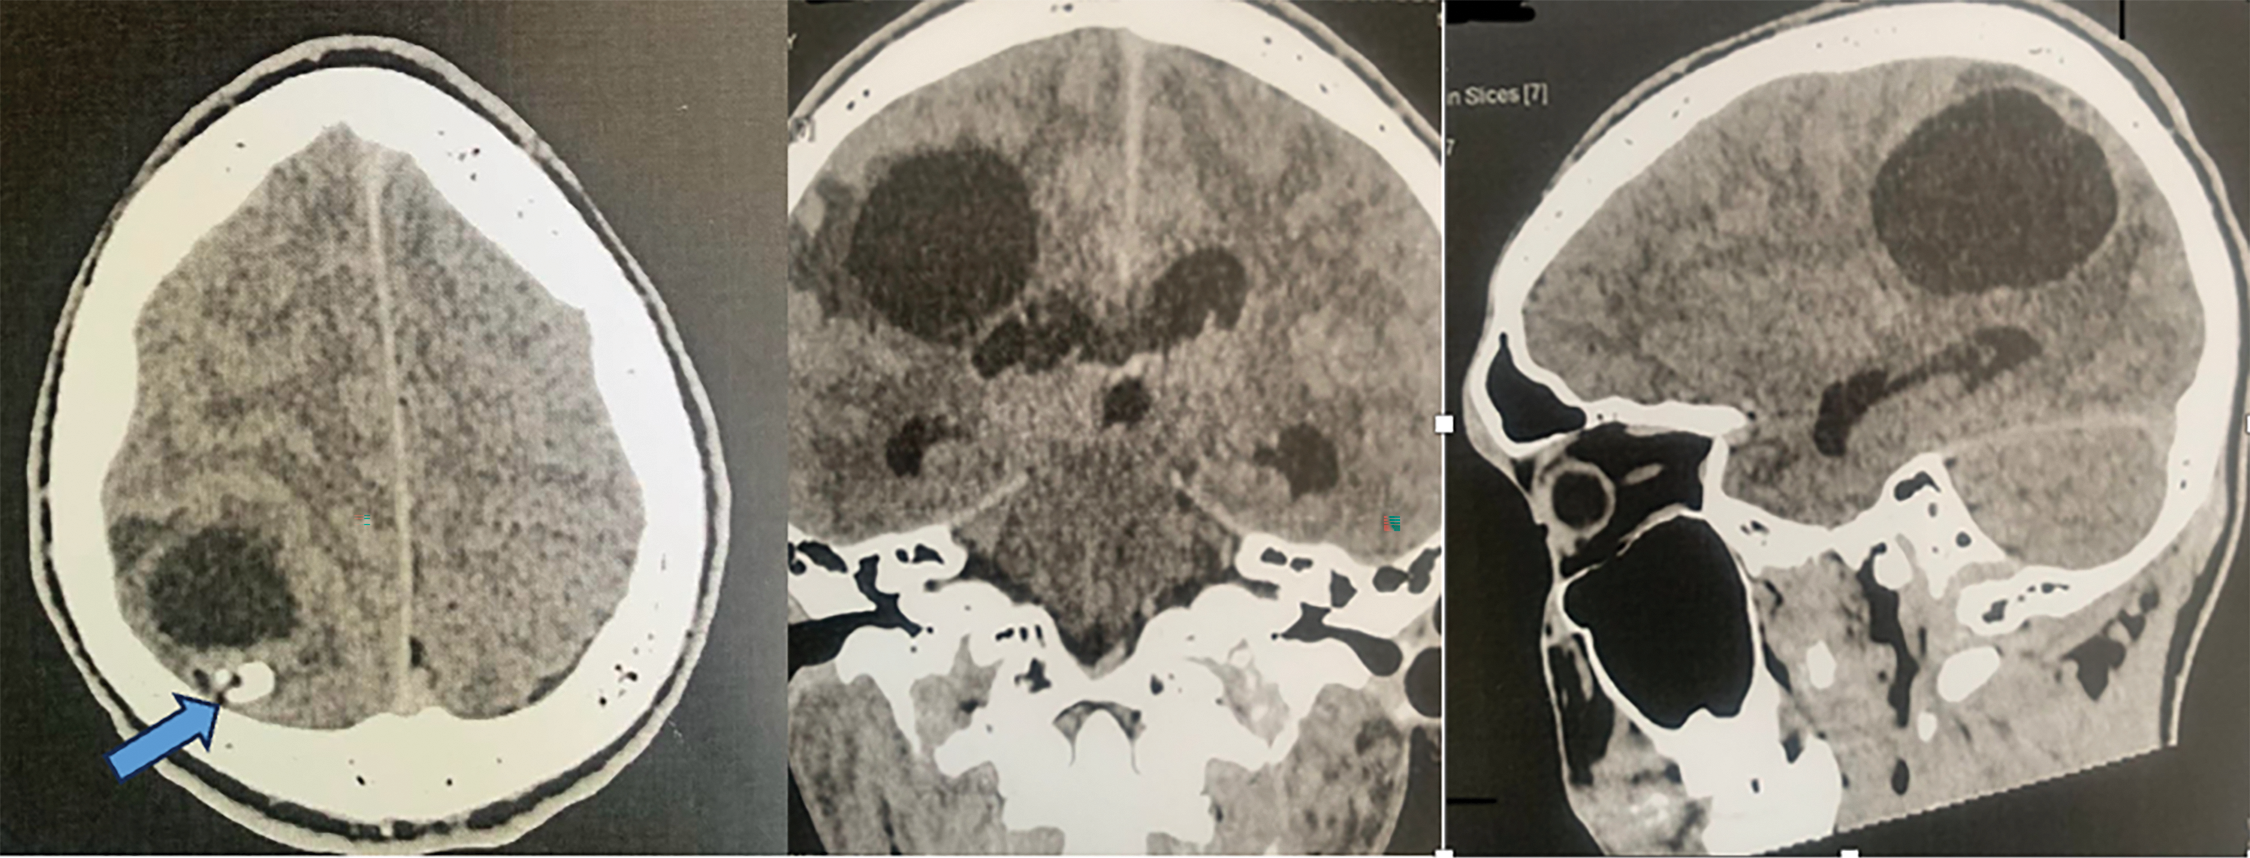

An MRI brain was performed in addition to the CT scan. It confirmed the voluminous cystic mass, intra parenchymatous of right parietal lobe, hypersignal in T2 without peri-lesional edema (Fig. 2); on the sequences T1 after injection of gadolinium it is an hyposignal (Fig. 3). It also objectified the compressive character of the lesion with effacement of the posterior horn of the right lateral ventricle. The blood count revealed a non-specific eosinophilia hyper. Hydatid serology was not performed.

Fig. 2. T2 sequence brain MRI visualizing a well-limited cerebral cystic mass.

Imaging is essential in the positive diagnosis and pre-therapeutic assessment of cerebral hydatic cyst. X-ray of the skull was not performed in our case; but authors report a voluminous calcification of the cranial vault visualized on radiography corresponding to a calcified cerebral hydatid cyst [12]. The current diagnostic tools are CT and MRI brain. The CT scan cerebral is the key examination, making a positive diagnosis of a hydatid brain cyst in almost all cases. It typically shows, as in our observation, a cystic mass, round or oval with clear contours, thin-walled, of density equivalent to that of the cerebrospinal fluid (CSF) associated with an important mass effect [1], [8], [9]. The cerebral hydatid cyst does not usually increase after injection and is not accompanied by perilesional edema [1], [10], [13]. The almost constant absence of peripheral enhancement by contrast product is explained by the thinness of the pericyst in the brain and by the adhesion of the hydatid membrane to the brain [9]. However, cases of hydatid cerebral cyst with contrast uptake and peripheral edema have been reported in the literature [9].

The hydatid cyst is often a single, intra-parenchymatous, supratentacular lesion, well limited, often spherical, with a density identical to that of cerebrospinal fluid, its wall is thin and is not enhanced by contrast, There is no peri-lesion edema [16]. Sub-tensor locations, especially cerebellar ones, are rare.

Brain MRI may be essential in the case of a reengineered cyst and will eliminate differential diagnoses. Problems of differential diagnosis may arise especially in cases of cyst rearrangement; these differential diagnoses are: cystic gliomas, arachnoid cysts, other infectious processes; the cyst wall is thick in these cases with or without contrast [19]. An MRI image of an intense iso cyst relative to the cephalospinal fluid in T1 and T2, with an intense hypo wall in T2, and without associated peri-lesional edema, will be characterized by a healthy cerebral hydatic cyst, this is the case in 75% of cases [4]. On the other hand, when there is a peri-lesion edema, hyperintense in T2, with a contrast taking of the wall, the hydatid cyst is said to be complicated, and then arises the problem of differential diagnosis [4]. Brain MRI would better locate and characterize the cerebral hydatic cyst than CT [20]. Other locations may be associated in about 30% of cases [21], including liver and lung particularly, they should be systematically searched for by performing an abdominal ultrasound and a chest x-ray.